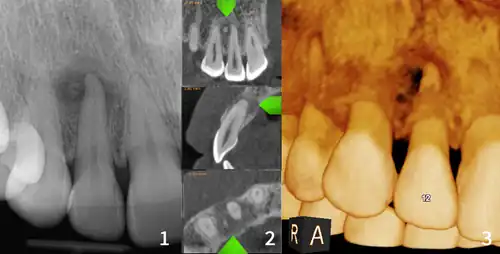

Diagnostic methodX-ray, CBCT scan, vitality testing of teeth

Diagnosis is based on clinical and radiographic observations, and in rare cases, biopsy may be performed.[3] Diagnosis is important so that the treating doctor does not confuse it for another periapical disease such as rarefying osteitis or condensing osteitis. Incorrect diagnosis could lead to unnecessary root canal treatments, or biopsy or surgical intervention which can be invasive and increase the risk of infection.[5] A pulp vitality test such as a cold test or electric pulp test can aid in diagnosis, since COD generally does not compromise pulp vitality.[6] COD can be found in individuals of all ages and ethnic backgrounds, but it has been observed more frequently in individuals of African, East Asian, and Asian descent.[7] Cone-beam computed tomography (CBCT) has proven useful in distinguishing between COD and periapical cysts, when examined with quantitative texture analysis using specialized software.[5]

xray and CBCT scans of periapical cemental dysplasia